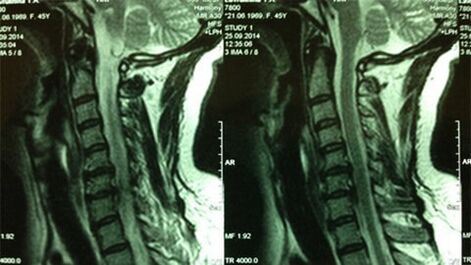

- X -ings du service cervical; Dans la phase initiale du processus, l'imagerie par résonance magnétique du département cervical sera plus instructive - garantira une affichage de haute qualité de tissus solides et mous - montrera la condition des disques intervertébraux, la présence d'ostéophytes, les déformations, les dommages aux roots nerveux et aux vestiges sanguins; évaluera l'état des ligaments, des muscles, du tissu osseux;